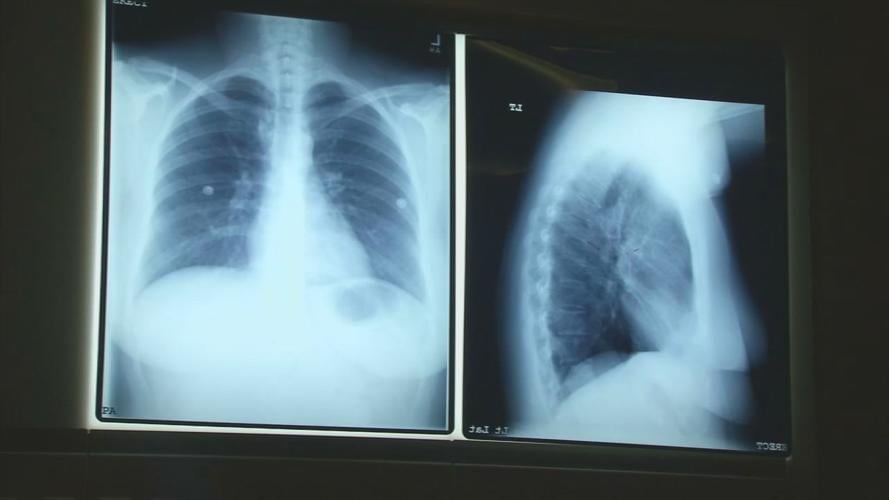

Experts said what makes lung cancer worse is that it initially doesn't show signs or symptoms, and is difficult to diagnose without screenings. That's why UofL Health is using November, which is Lung Cancer Awareness Month, to stress the importance of getting screened.